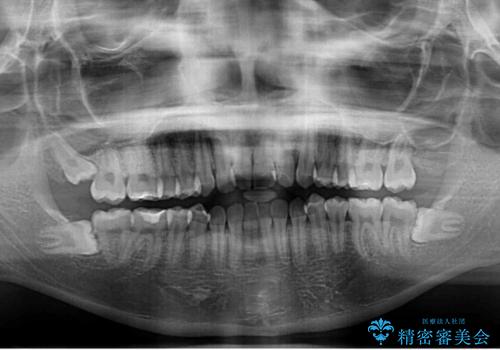

- 前歯のデコボコを気にして来院された患者様です。

マウスピース矯正のような自己管理の煩わしさがなく、早く治療を終えたいとのことで、ワイヤー装置による矯正治療を行うこととしました。

当初予定通り、1年で治療を終えることができました。